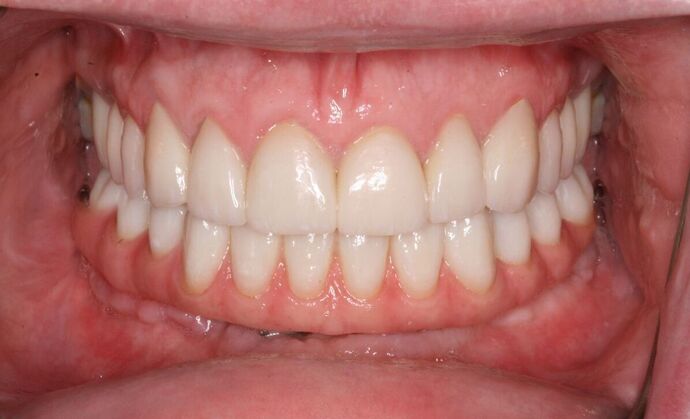

All-on-4/ Full Mouth Dental Implants / Teeth in a Day: Case 18- Upper crowns and Lower All-on-4 Bridge

This patient, a mental health counselor was frustrated that despite taking care of his teeth all his life, he ended up having several cavities that made him lose several of his lower teeth. His cavities in his upper natural teeth was manageable through crowns and his remaining lower teeth were extracted and new implants and teeth were installed in one day without the need for any bone grafting.

Procedures : extractions, implants, All on 4 , Teeth in a day, no bone grafting and full mouth reconstruction with monolithic zirconia bridges.